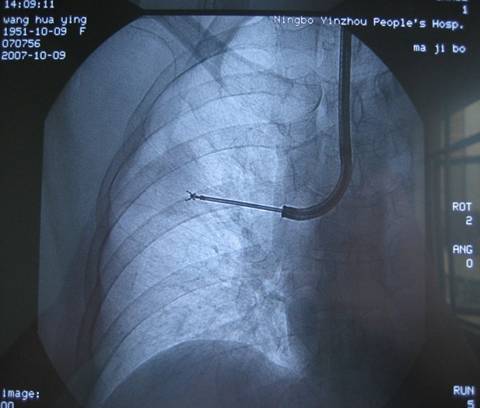

经支气管镜肺活检术

(transbronchial lung biopsy)

经支气管肺活检主要用于肺部周边部位局限性病变,需在放射科

X

线或

CT

引导下进行。

在

线透视或

引导或定位下,支气管镜先端部固定于段支气管口,将活检钳送至病变部位,并确定活检钳的位置准确无误,钳取病变组织,进行诊断。

图片: